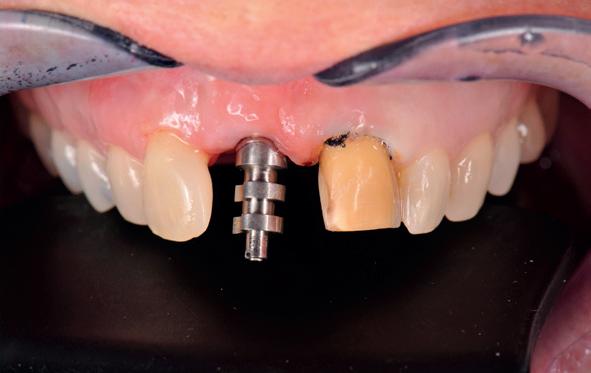

Digitale planning en directe plaatsing

In het huidige tijdperk zijn we vooral bezig met topdown planning, waarbij wij het eindresultaat simuleren en de bijbehorende behandeling met CAD/ CAM-technieken voorbereiden. De implantaten worden “dwingend” geplaatst door een tevoren gemaakte mal, waarbij het soms al mogelijk is meteen een tijdelijke of zelfs “definitieve” voorziening te plaatsen (afbeelding 15).